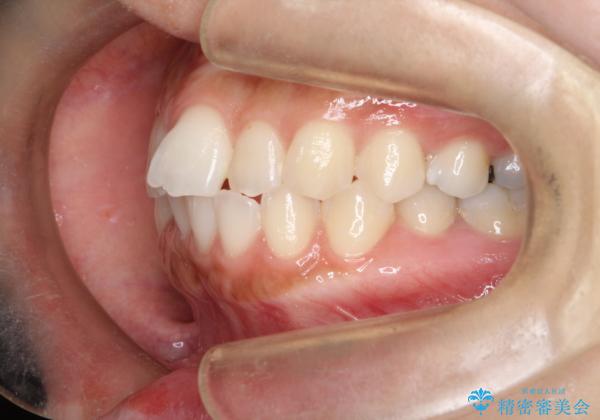

口元をさげたい ワイヤーによる抜歯矯正

- 口元が出てるのが気になるとのことで来院されました。

上下左右前から4番目の歯を抜歯して前歯を後方に下げて、口元を下げる計画としました。

口元を大きく改善したい場合は抜歯が必要となることが多いです。